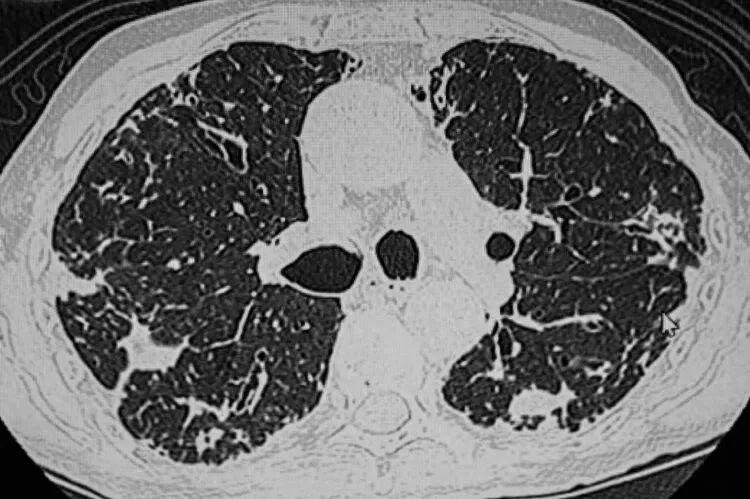

第二天就请假去了医院检查,结果发现结节已经增长到了14mm,且出现了实性成分。后续的增强CT、肿瘤标志物检查高度怀疑是恶性肿瘤,刘先生被安排入院进行相关治疗。好在刘先生的病程还处于早期,可以进行手术治疗,术后他很快就康复出院了。

首先,现在的医学影像技术越来越发达,检查时的分辨率较高,一些隐匿性、之前难以发现的病灶也可以及时发现,这样一来检出结节的几率自然也会增加。

很多患者在罹患肺结节后,身体没有任何不适症状,这种情况下只能通过胸部CT检查来发现结节。

当胸部CT检查普遍后,很多人会被检查结果上的肺结节结果吓到,担心结节会发生癌变。在中国第31个全国肿瘤防治宣传周上,中国抗癌协会整合肿瘤分会青委会主委薛建新明确指出,体检中查出的肺结节95%为良性,只有5%有恶变的可能性。

• 长相:结节有毛刺征、分叶状、血管集束征、胸膜凹陷征等特征,恶性程度较高

• 密度:从危险程度上来看,是混合型>磨玻璃>实性